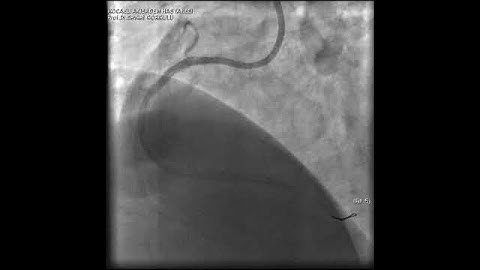

Complex PCI for RCA CTO with bifurcation at distal cap video 1